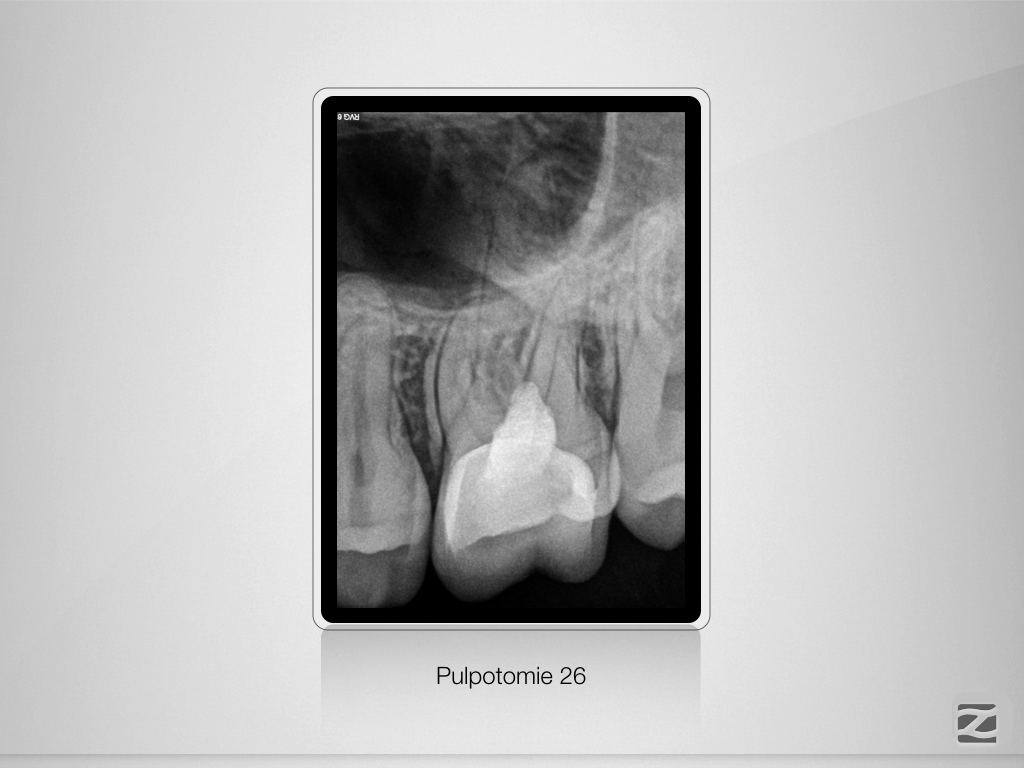

Alternativlos?